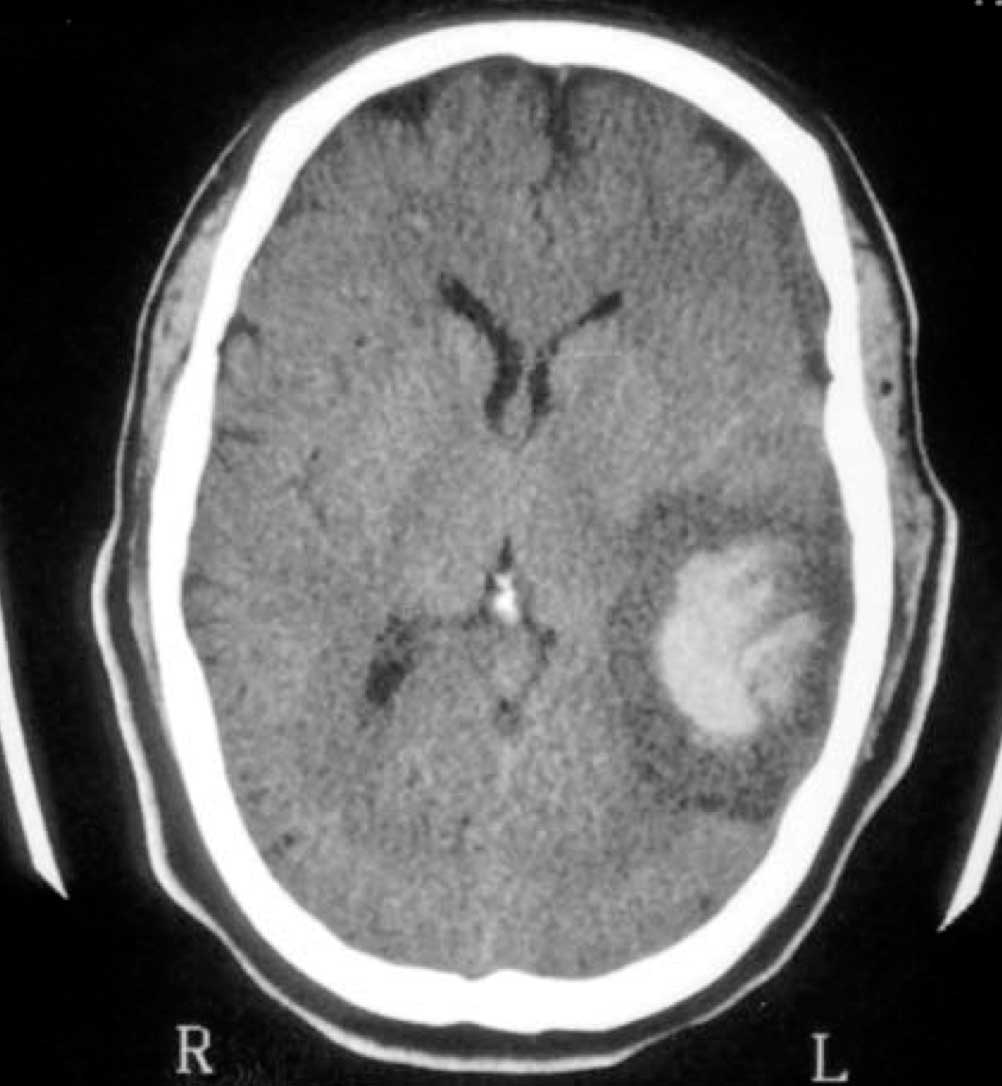

O propósito desse artigo é descrever as características clínicas e patológicas de angiossarcoma metastático no sistema nervoso central. Apenas alguns casos de metástase cerebral de angiossarcoma do coração foram relatados na literatura; especificamente relacionados à hemorragia intracerebral. Um caso de angiossarcoma cerebral secundário de coração em um homem de 33 anos é apresentado. Os sintomas iniciais são dor de cabeça, vômitos, letargia e afasia. Havia uma massa no lobo temporal esquerdo com hemorragia e edema na tomografia computadorizada(CT). Após 24 horas, o quadro neurológico piorou e um outro exame de TC mostrou um sangramento reincidente na área do tumor. Ele foi submetido a uma craniotomia de emergência, mas morreu 2 dias depois. Considerando a maior sobrevivência de pacientes com sarcoma devido às novas modalidades de tratamento, a incidência de metástase cerebral pode aumentar, uma abordagem preventiva melhor e mais agressiva. Além disso, devido à natureza hemorrágica de tais lesões, nós sugerimos a cirurgia imediata para impedir uma evolução rápida e letal por causo de sangramento reincidente.